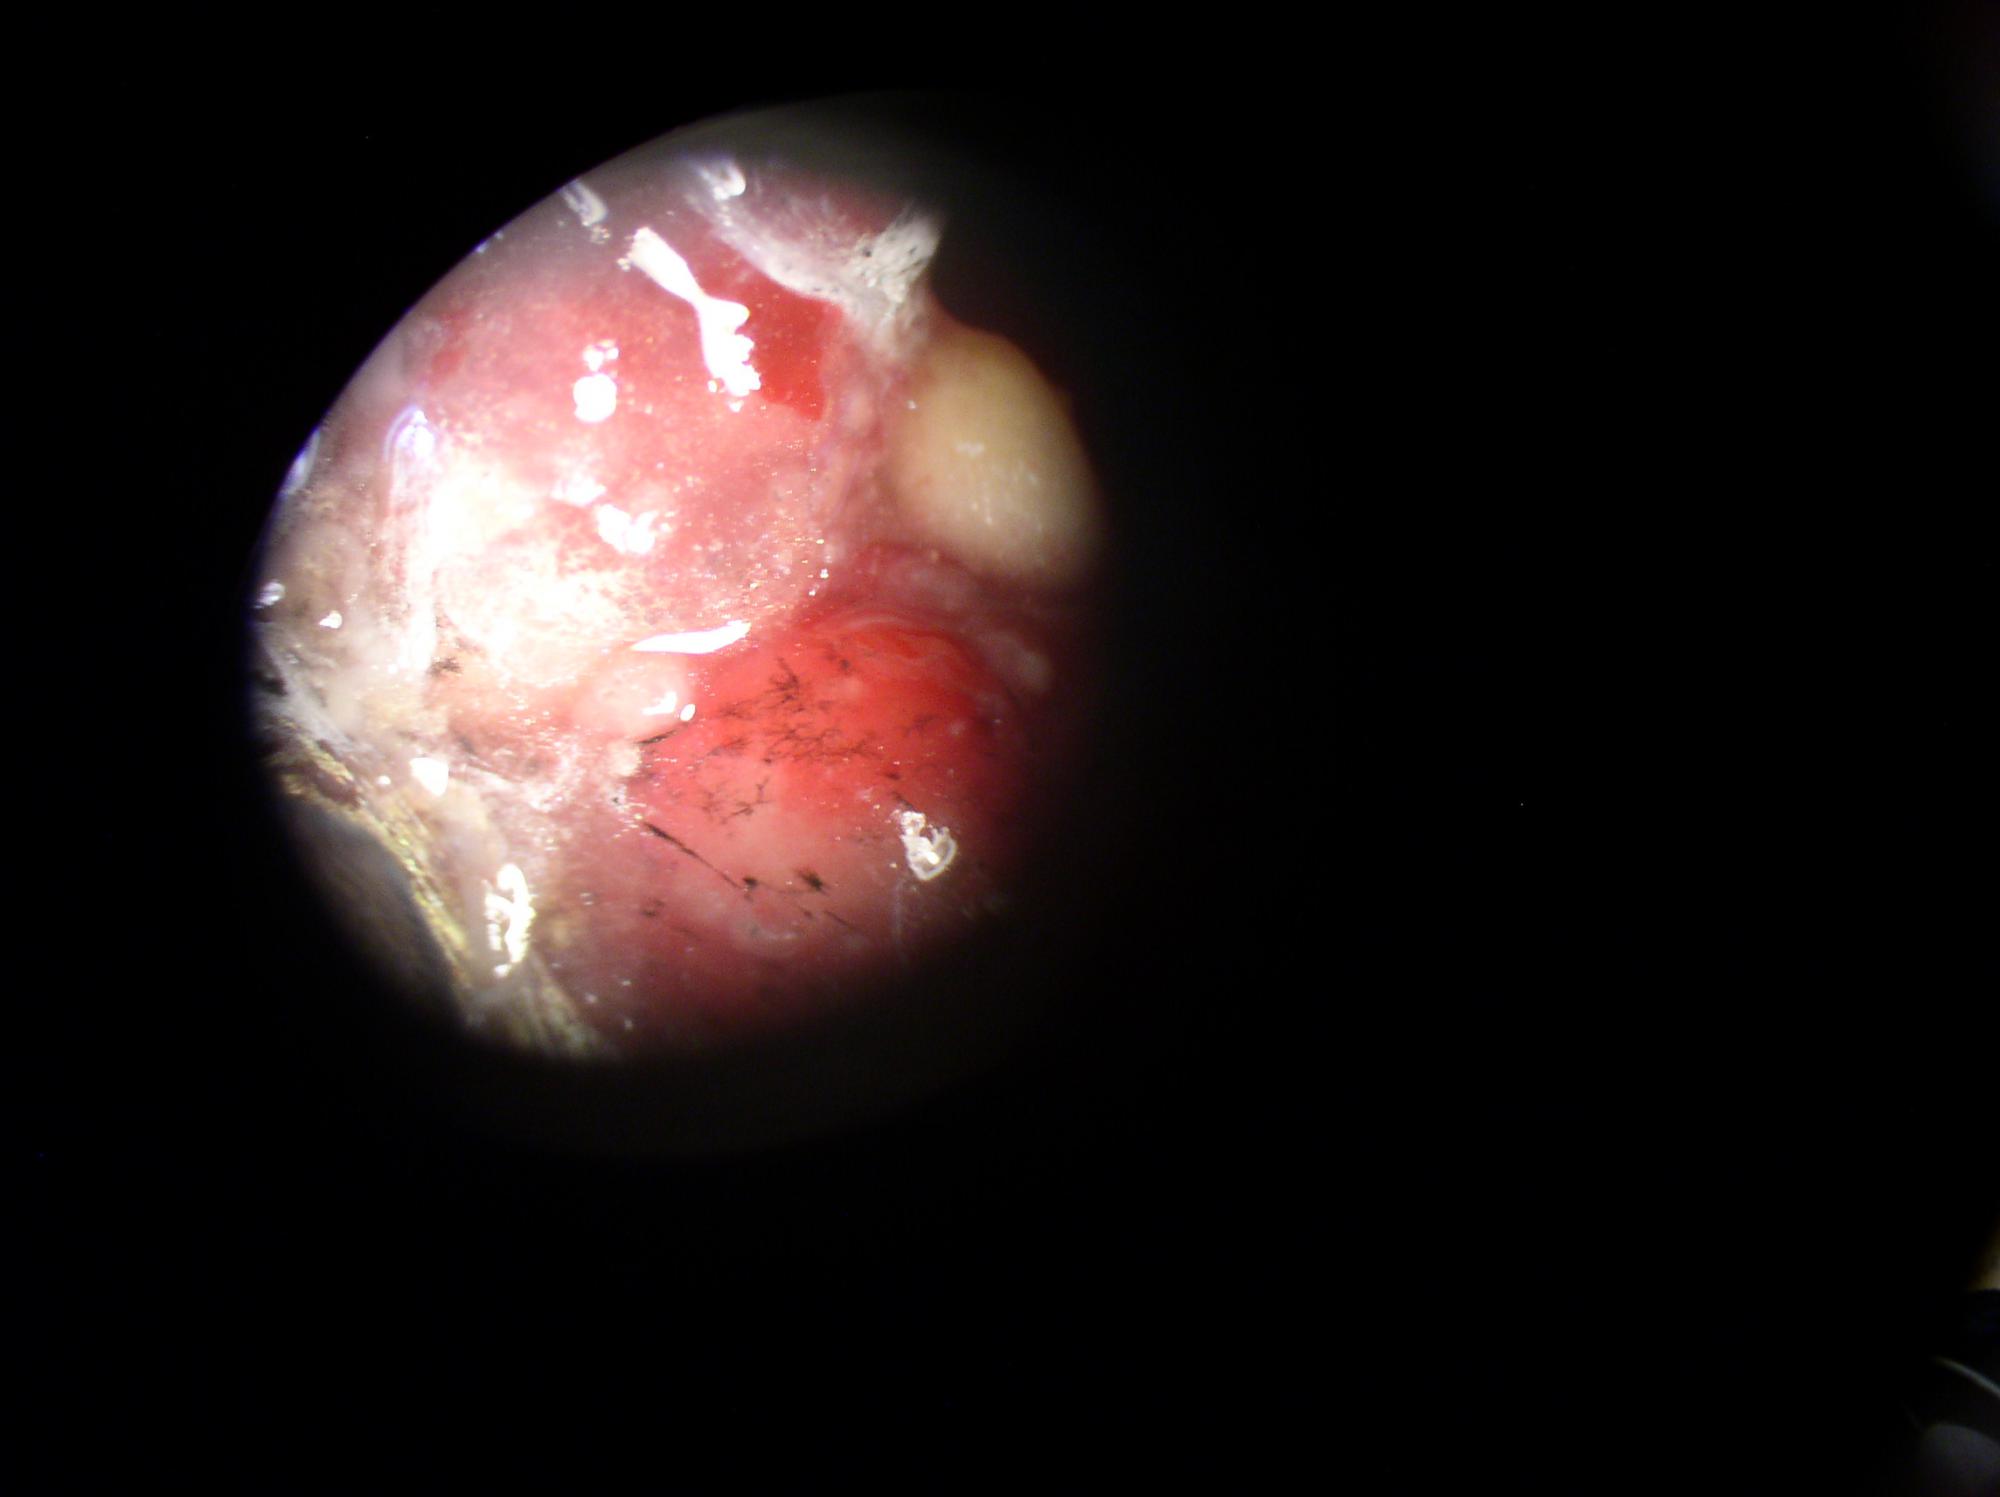

Вот фото, которые удалось сделать дома.

На фото:

1,2,6 - целые капсулы.

Они блестящие, покрыты некой плёнкой.

3-5 - разрезанные капсулы.

Внутренняя структура нопоминает мокрый хлебный мякиш.

В этом "мякише видны чёрные включения, как кусочки грязи.

7,8 - кожа возле жабер.

На коже видны участки без кожи.

9,10 - внутренние органы.

Справа вверху видна капсула.

Она там и была.

И видны чёрные сеточки.

11 - общий вид.

Видны многочисленные капсулы.

больше похоже на жировики. При большем увеличении не микроскопировали?